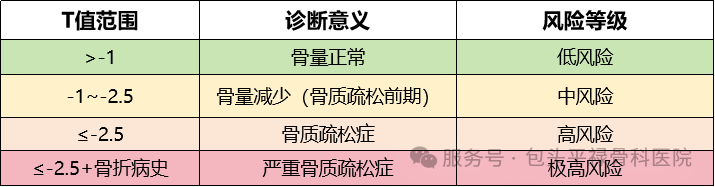

确诊检查

根据双能X线骨密度仪(DXA)检测结果T值:

注:骨质疏松的诊断不能仅依赖骨密度检测,还需结合临床表现、骨折史和实验室检查综合判断。因此,当自测发现风险因素时,应及时就医进行全面评估。